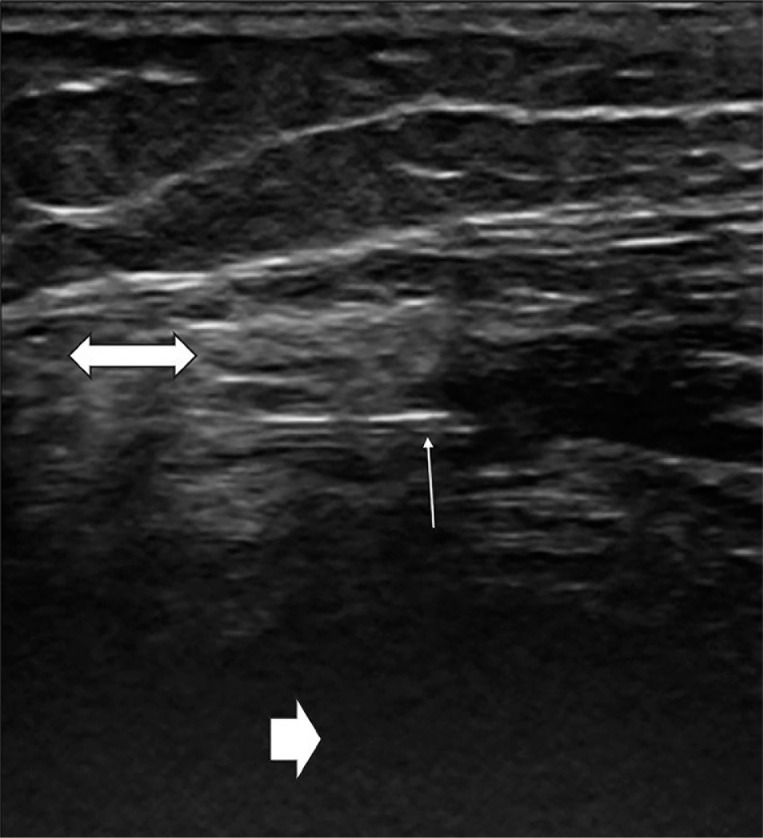

放射滑膜成形术是一种治疗炎性关节疾病的微创方法。它是手术滑膜切除术的一种替代方法,当全身治疗和关节内糖皮质激素注射失败时使用。本文综述了该方法在各种炎性关节疾病中的疗效。在PubMed、Embase、Web of Science和DOAJ数据库中进行系统的文献检索。根据炎症类型和关节破坏程度的不同,治疗的有效性为50-80%,在血关节病中甚至高达90-100%。目前的研究表明,这种疗法是安全的,几乎没有副作用。由于其流动特点,它为患者提供了长期的成本效益,不需要康复,并减少了其他疗法的使用。此外,它可以作为一种独立的治疗类型,也可以作为复杂治疗的一部分。鉴于其好处,该方法应得到各领域专家的考虑。

Radiosynoviorthesis is a minimally invasive treatment for inflammatory joint disorders. It is an alternative to surgical synovectomy and is used when systemic treatment and intraarticular glucocorticosteroid injections have failed. This literature review summarizes the effectiveness of this method in various inflammatory joint disorders. A systematic literature search was performed in the PubMed, Embase, Web of Science and DOAJ databases. Depending on the type of inflammation and level of joint destruction, the effectiveness of therapy is 50-80%, up to even 90-100% in hemarthrosis. The present study demonstrates that the therapy is safe, with almost no side-effects. It provides long-term cost-effectiveness for patients due to its ambulatory characteristics, does not require rehabilitation, and leads to reduced use of other therapies. Moreover, it may be used as an independent type of therapy as well as a part of complex treatment. Given its benefits, the method should be considered by specialists of various fields.